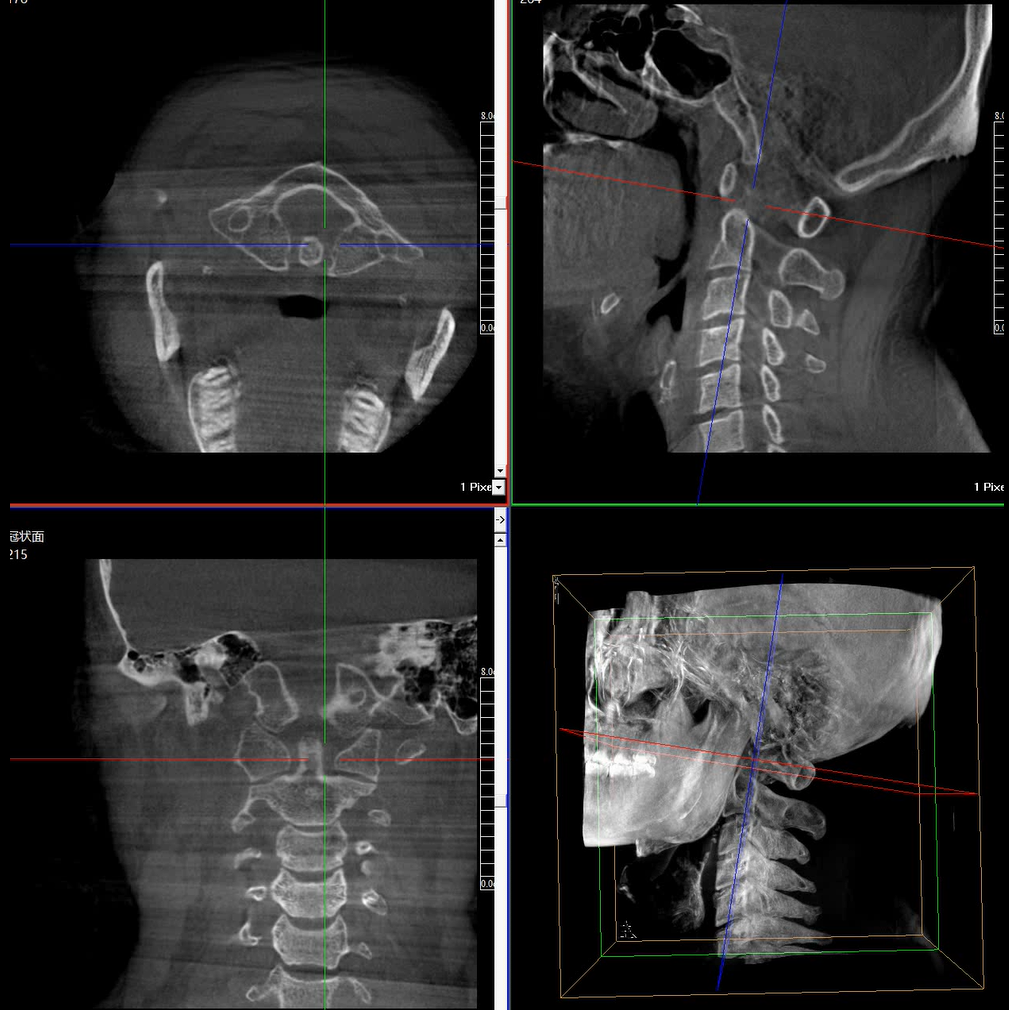

術(shù)中三維成像和橫斷面圖像提供多角度的手術(shù)診斷信息,輔助醫(yī)生進行術(shù)中評估判斷,諸如骨折復(fù)位情況和內(nèi)植入螺釘?shù)某叽绾臀恢?,輔助手術(shù)更好地完成。

提供更大的術(shù)中三維成像視野,采集更多圖像信息,可一次拍全全段頸椎、全段腰椎、七節(jié)胸椎、雙側(cè)骶髂關(guān)節(jié)、股骨頭及單側(cè)盆骨。

在C臂掃描過程中,始終保持拍攝主體處于射線束的中心,避免了序列圖像采集過程中的橫縱方向運動,減少相對運動造成的運動偽影。